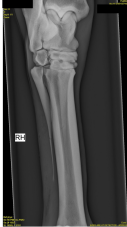

På dette røntgenbillede findes osteochondrose på et prædilektionssted i talocruralleddet hos hest. Hvilke andre prædilektionssteder for osteochondrose i talocruralleddet hos hest findes der?

1 Laterale trochlea, mediale malleol

2 Distale intermediærkam af tibia, laterale trochlea

3 Mediale kondyl, mediale malleol

4 Tuberositas tibia, distale intermediærkam

Det rigtige svar er 1